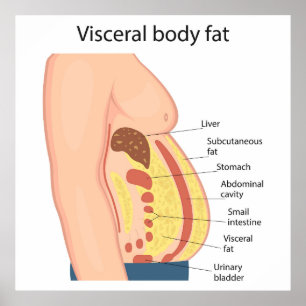

Poster Gordura do corpo visceral

Preço117,00 €